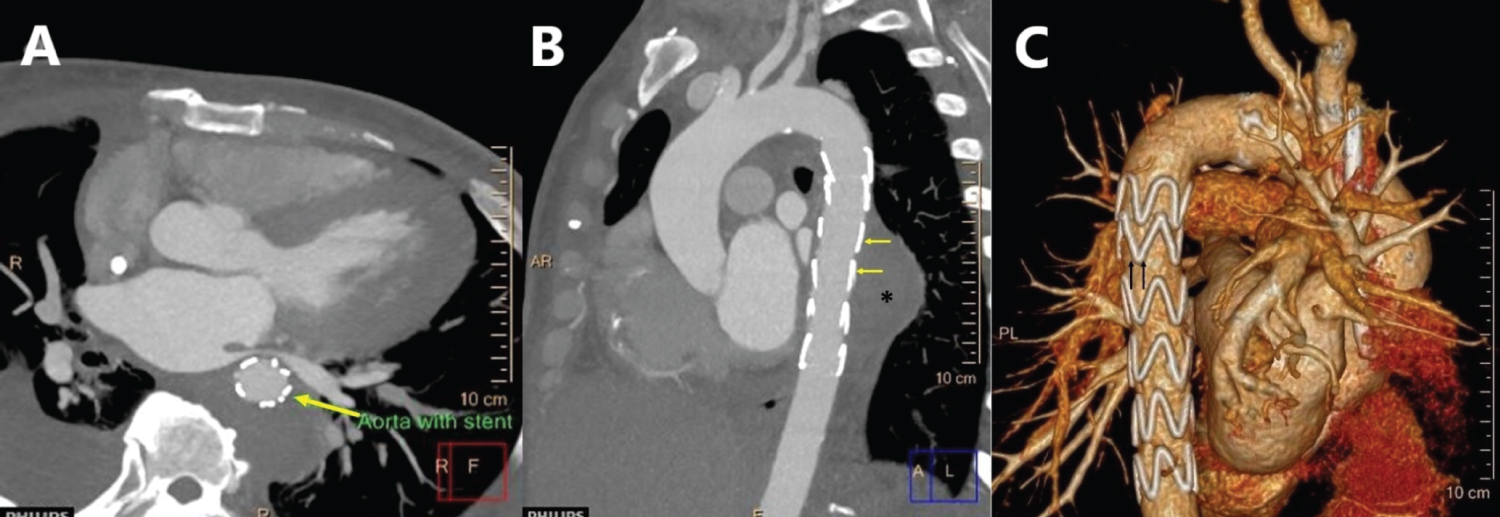

50-year-old woman with end-stage renal failure on haemodialysis presented with chest pain. She was recently treated with methicillin-resistant Staphylococcus aureus bacteraemia secondary to tunnel line infection. Transthoracic echocardiogram demonstrated a linear structure in the descending thoracic aorta suspicion for an aortic dissection (Figure 1). Computed tomography (CT) thoracic aorta (Figure 2) showed a large descending thoracic aortic aneurysmat the T7/T8 level. Because of her comorbidities, a stent was deployed in view of high risk of perforation and she was placed on prolonged antibiotics.Post-stenting CT scan (Figure 3) a few weeks later showed a patent stent and the aneurysm appeared successfully excluded.

Figure 3: (A & B) Thoracic aortic stent graft demonstrated in situ (yellow arrow). The site of previous aneurysm (asterisk) now appears successfully excluded with no contrast enhancement demonstrated within; (C) Volume rendered image of the CT thoracic aorta demonstrating the endovascular thoracic aortic stent graft (black arrows).